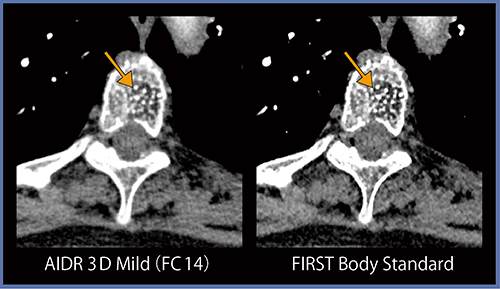

●症例5:骨転移

肩口のレベルはストリークアーチファクトが発生しやすいが,FIRSTでは低減している(図6)。転移性腫瘍の脊柱管内に軽度突出している部分(←)も,AIDR 3Dに比べてFIRSTでは辺縁がきれいに描出されている。

図6 症例5:骨転移